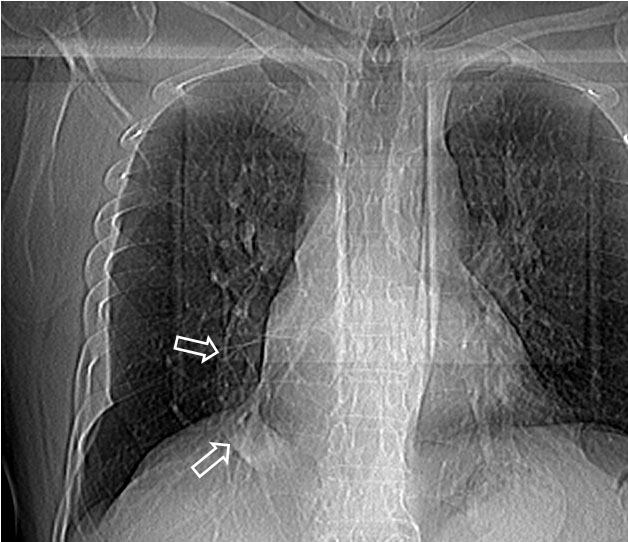

SIGNO DE LAS ASTAS DE CIERVO

Signo de hipertensión venosa pulmonar en la radiografía posteroanterior de tórax. Consiste en el engrosamiento de las venas de los campos pulmonares superiores (flechas) por redistribución del flujo, normalmente dirigido hacia las bases de forma preferente. Si la presión venosa pulmonar no se controla con este mecanismo fisiopatológico, se produce el edema intersticial y, finalmente, el edema alveolar.